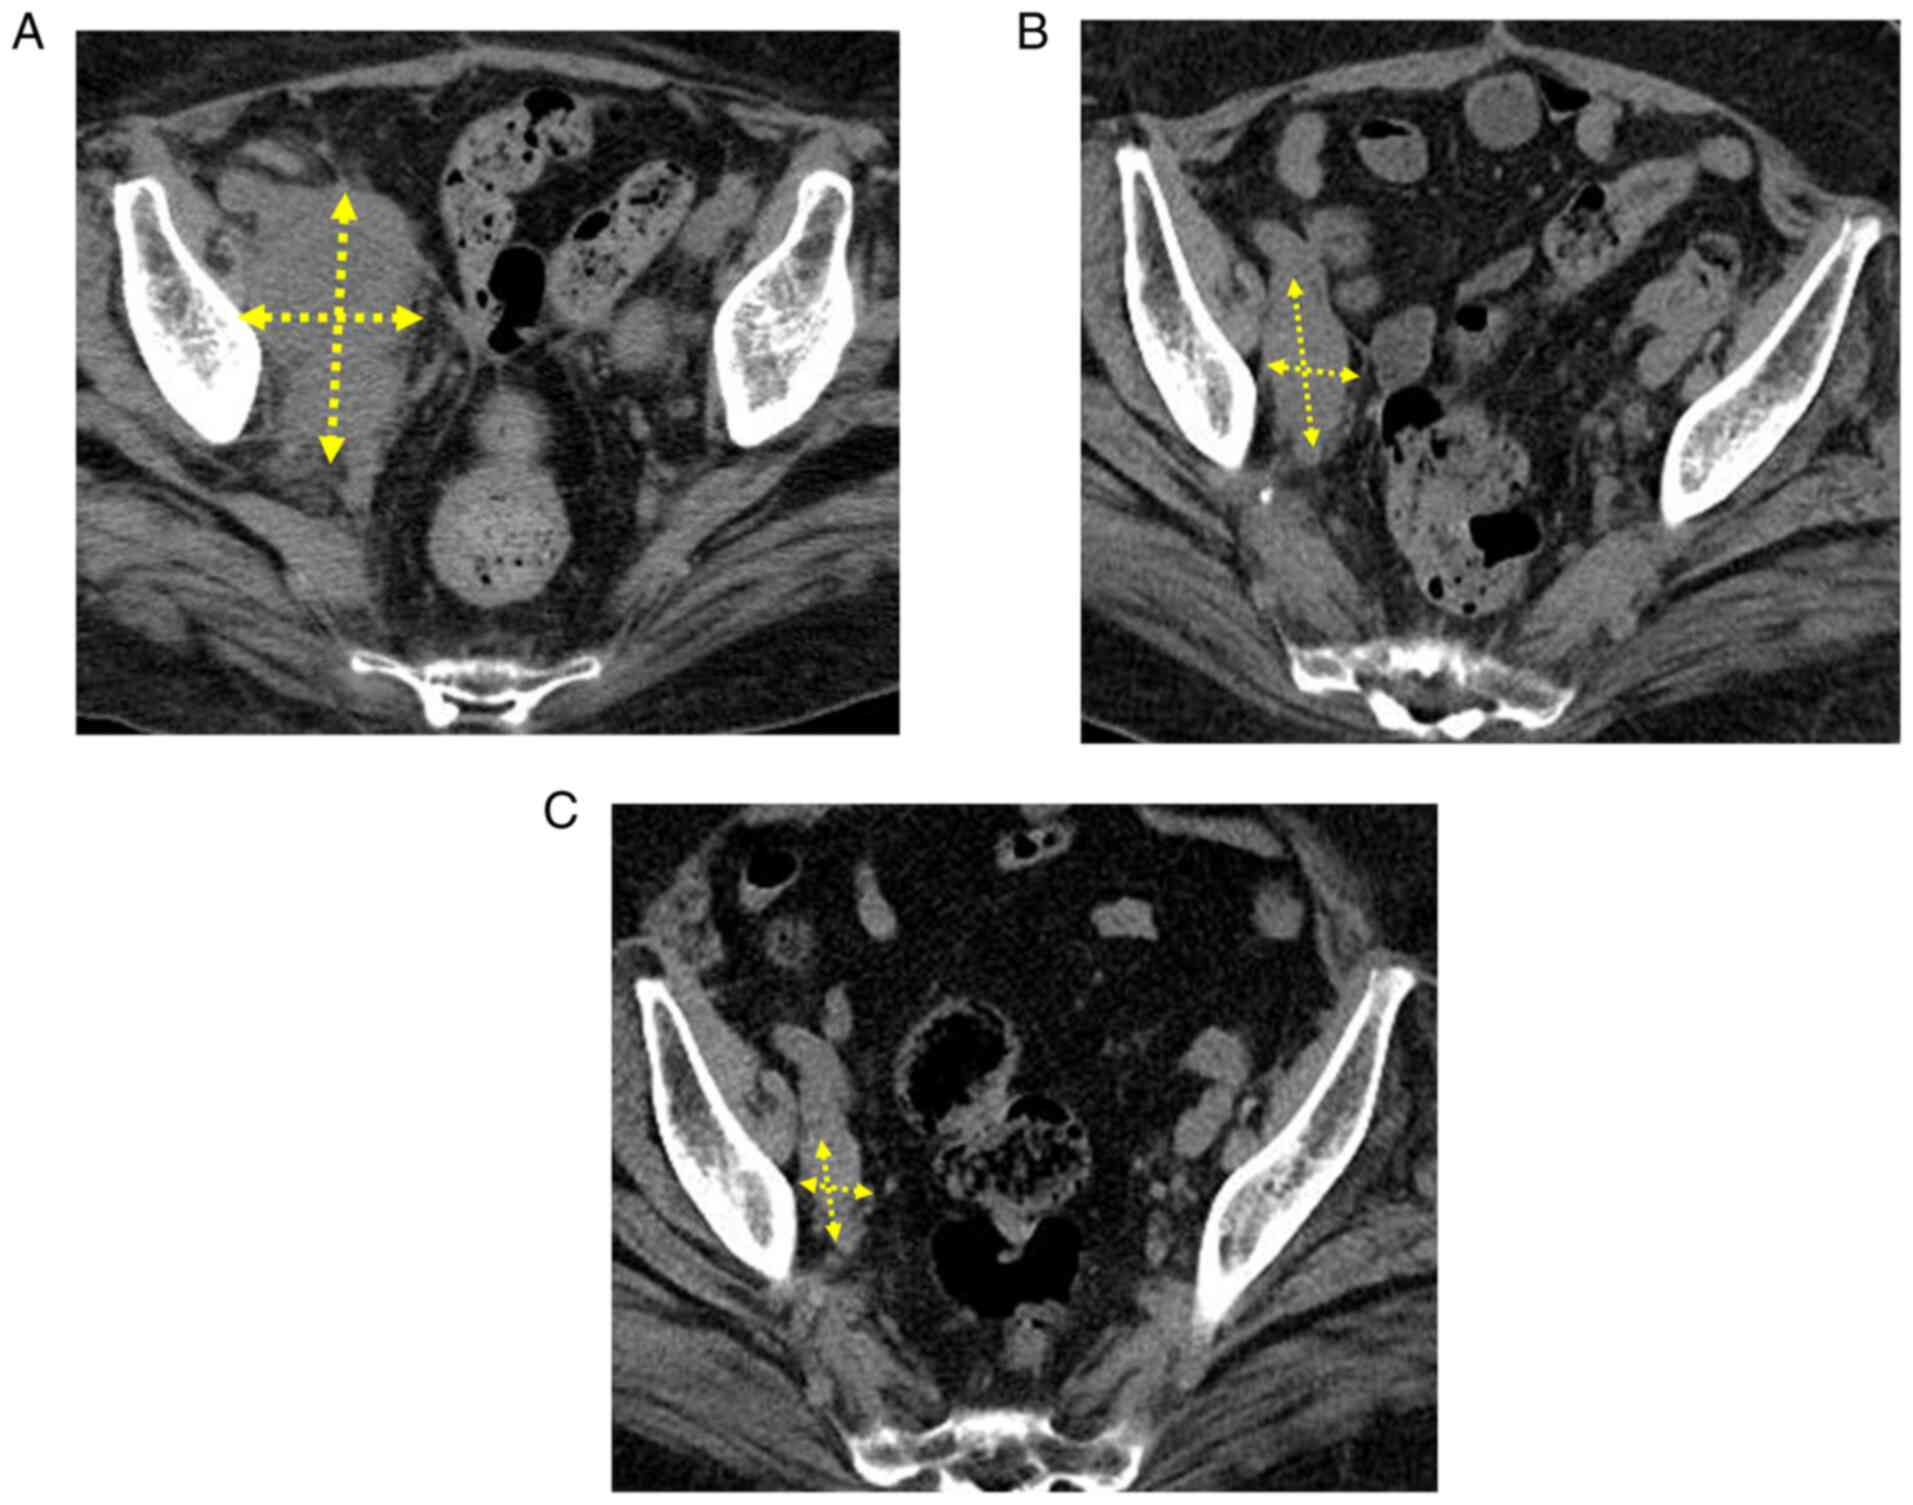

Durable response after the discontinuation of pembrolizumab treatment due to an adverse event in a patient with advanced endometrial cancer: A case report

The persistence of antitumor effects has been reported after the completion of treatment with immune checkpoint inhibitors (ICIs) for various types of carcinoma, such as malignant melanoma, exhibiting a durable response. A durable response has also been noted after the discontinuation of treatment at an early stage due to adverse events, including in renal pelvic cancer, pancreatic cancer and intrahepatic cholangiocarcinoma; however, to the best of our knowledge, a similar case report has not yet been published in the malignant gynecological tumor field. The present study described a patient with refractory advanced endometrial cancer in whom the administration of pembrolizumab was discontinued after the completion of the 7th course due to renal dysfunction; however, persistent tumor‑reducing effects and decreases in the levels of tumor markers were noted for more than 18 months after the cessation of treatment. Pembrolizumab may be continuously administered to some patients for a long period, whereas a durable response is achieved by others even after its discontinuation at an early stage; therefore, difficulties are associated with selecting an appropriate duration of administration. Further studies are required to search for biomarkers that facilitate high‑accuracy effect predictions, and to establish an optimal administration period in consideration of specific adverse reactions to ICIs and cost‑effectiveness.

Figure 2